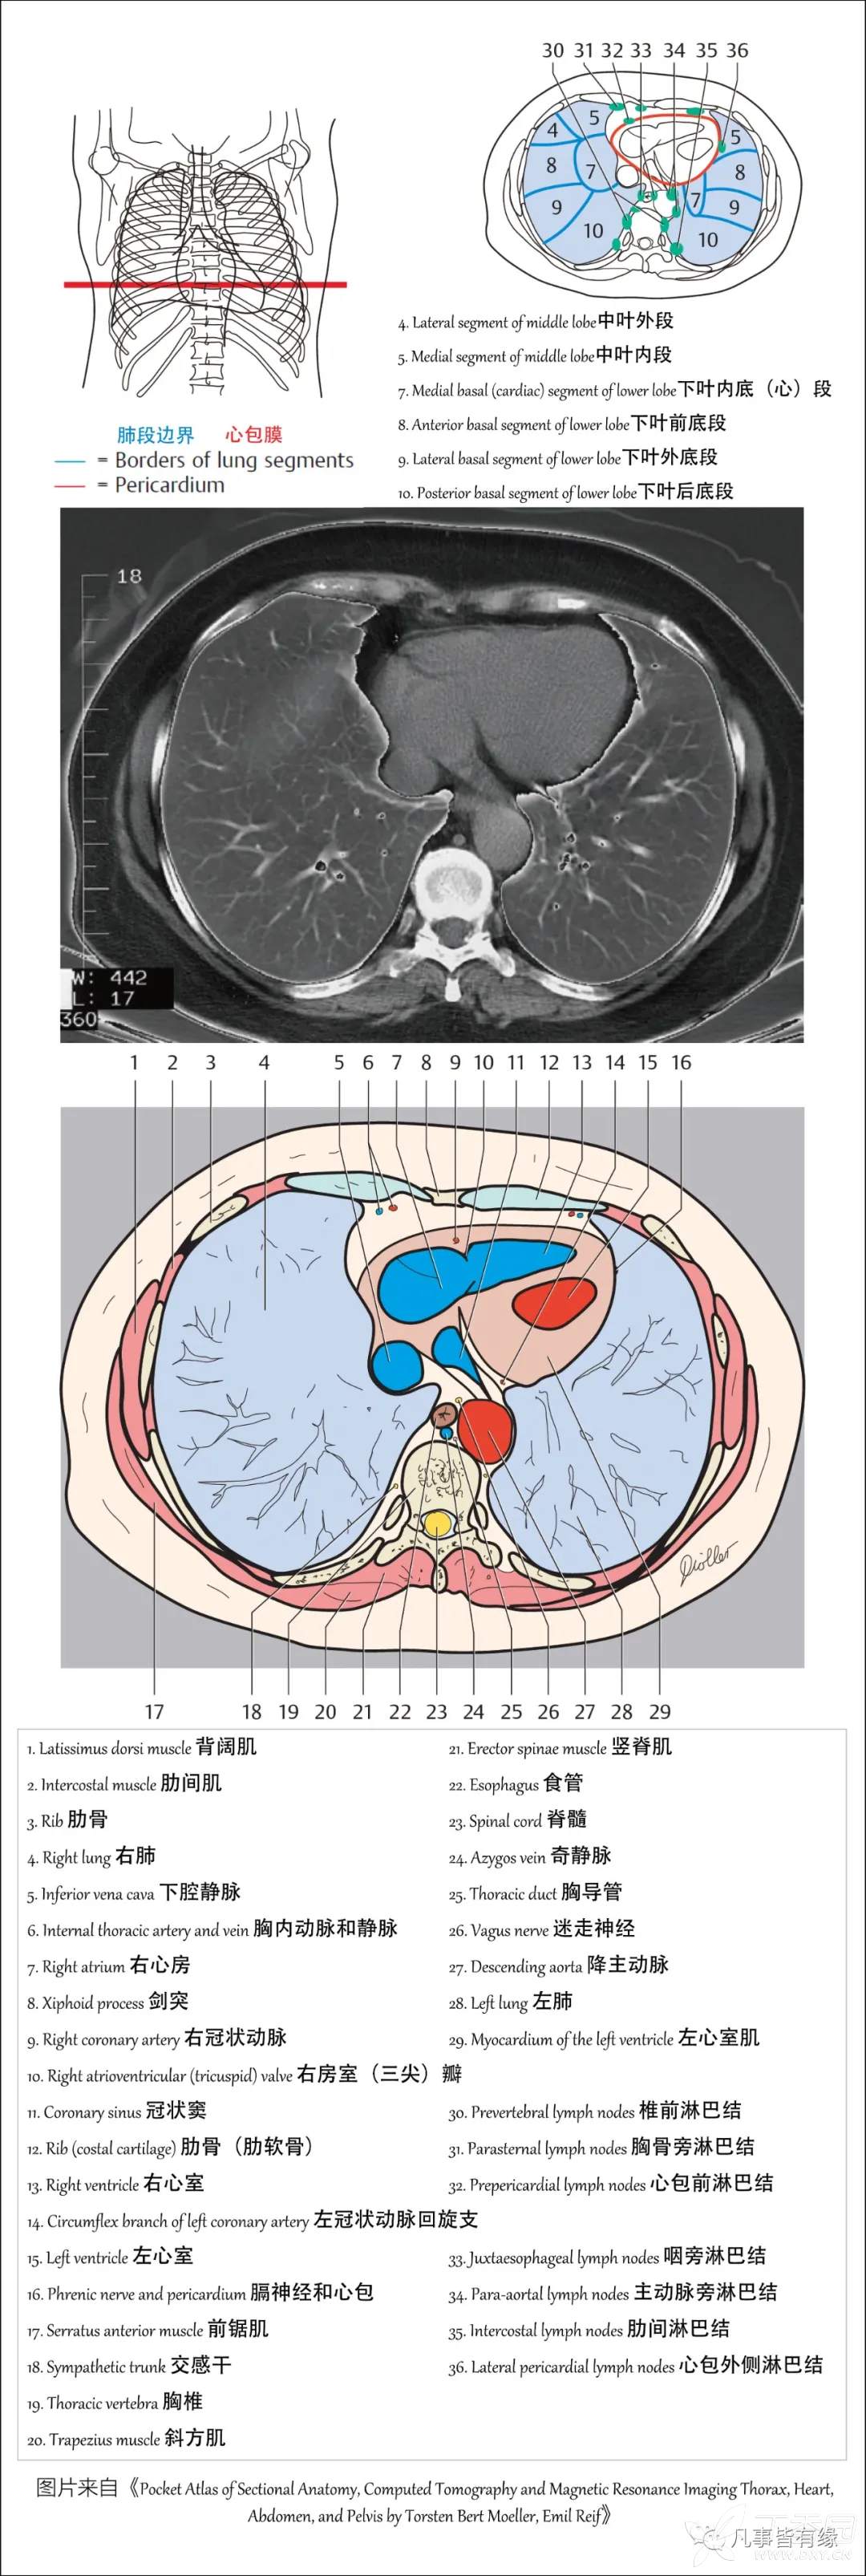

(一)胸部CT轴位断层解剖: